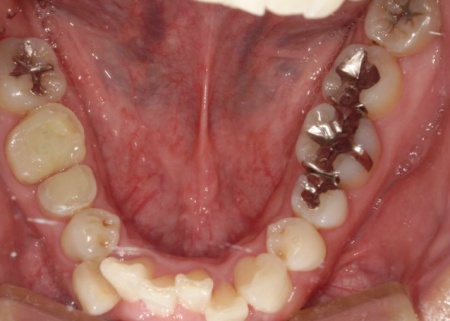

40代男性 温存が難しい複数の歯を抜いてインプラントブリッジで修復した症例

拝見したところ、上左右の奥歯には、歯が失われていたり欠けたりしている部位が複数確認されました。

そこで、詳しく検査を行った結果、欠けたり傷んだりしている歯が複数見つかり、さらに歯茎や歯を支える骨にも問題が生じていました。

とくに、右上奥歯は前から4番目と6番目の歯、左上奥歯は前から4番目・5番目・6番目・8番目の歯が著しく傷んでおり、温存が難しいと考えられます。

また、右下の一番奥の歯(親知らず)は歯の根だけが残り、細菌感染が広がるリスクが高い状態です。

その一方で、上前歯や右下奥歯は、適切な処置を行うことで温存できる歯も複数確認できました。

以上のことから、口腔内の状態を改善するためにも必要に応じて抜歯を行い、欠損部位を補う治療が必要だと診断しました。